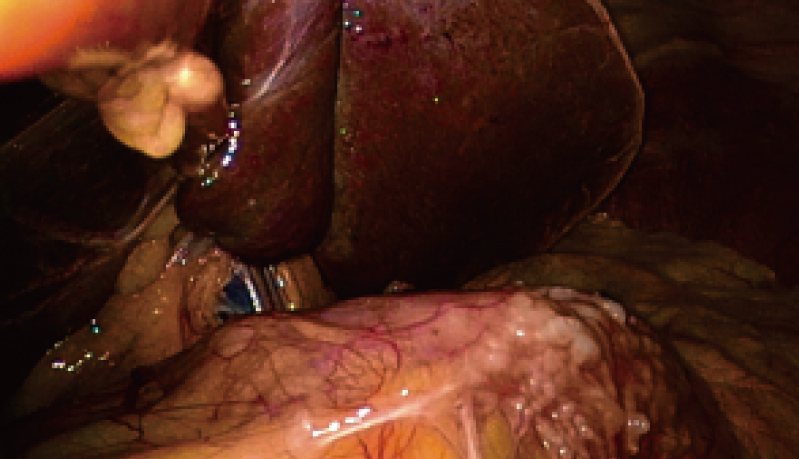

强大的图像后处理技术

• 大出血情况下亮度自动调高,迅速找到出血点

• 图像后处理优化技术,减少录像残影

• 针对四种不同术式的图像预设